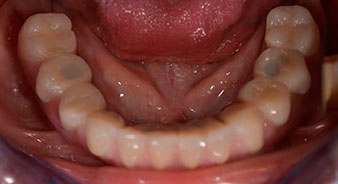

The 64-year-old patient presented with residual dentition of teeth 38, 33 and 43 and a clasp denture in the mandible (Fig. 1 and 2).